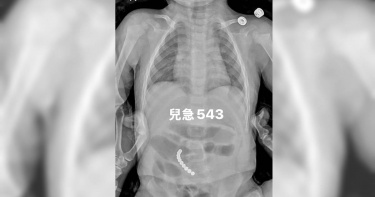

家長要小心!兒科醫師廖穗綾分享一個驚險案例,一名1歲多的幼童被阿嬤餵食整顆花生,幾天後出現咳嗽、喘鳴聲等症狀,送醫檢查驚見「肺部已經開始塌陷」。為了取出這顆卡死在氣管的異物,醫療團隊耗時近2小時,在狹小氣道裡反覆嘗試才成功夾出。看著住進加護病房的孩子,醫師忍不住怒喊:「到底為什麼要餵小小孩吃整顆花生?」基隆長庚醫院兒科教授級主治醫師廖穗綾今(12)日在粉專發文指出,上週遇到一名緊急送來的1歲多幼童,據了解,孩子在3、4天前被阿嬤餵食了花生,隨後開始出現咳嗽與喘鳴聲,雖然剛開始症狀不明顯,但隔天追蹤X光發現,「肺部已經開始塌陷」,這絕非小事。當晚該童轉入加護病房,廖醫師的丈夫賴醫師緊急召集加護病房團隊與資深技術員,準備透過支氣管鏡取出異物。然而,手術過程極度艱難,廖穗綾透露那顆花生已經卡了三天、肉芽長出來,「整顆又大又肥,死死塞住支氣管」;賴醫師更直言,他從來沒有遇過這麼困難的案例。廖穗綾續指,醫師在孩子狹小的氣道裡反覆嘗試將近2個小時,就在幾乎快要放棄時,那顆「會跳舞的花生」終於彈動了一下,醫療團隊隨即成功網住、夾出,那一刻大家才鬆了一口氣。雖然孩子成功救回,但廖穗綾忍不住怒轟這已不是第一個案例,甚至今日又看到兒科急診醫師吳昌騰分享其他孩子因被餵食花生而進開刀房。針對許多家長常說「只吃一顆而已」、「我有在旁邊看著」、「我們以前都這樣長大」,廖穗綾指出,醫療現場看到的卻是「氣道發炎腫脹」、「肉芽生成」、「肺部塌陷」,最後只能住進加護病房插氣管鏡。「我們到底還要講幾次?到底為什麼要給小小孩吃整顆花生?」廖穗綾強調,小小孩的吞嚥與咀嚼能力尚未成熟,兩者間協調不夠穩定,若吞嚥瞬間聲帶剛好打開,比較硬且不易咬碎的食物就可能滑入氣管中。廖穗綾提醒家長,花生、堅果類、湯圓、硬芭樂、椰果,以及任何「硬、滑、不易咬碎」的食物,請至少等到孩子3至4歲以上再嘗試。